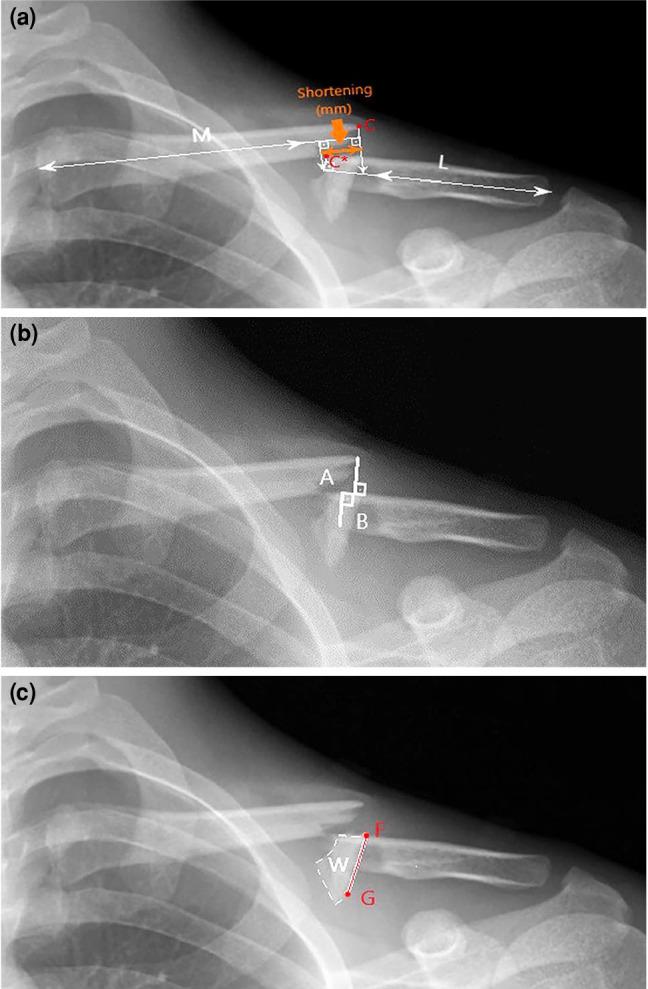

Objectives: The aim of this study was to evaluate whether fracture shortening, displacement, and the length of butterfly fragments were reliable radiographic indicators of secondary healing failure in displaced midshaft clavicle fractures with butterfly fragments and to determine whether these radiographic parameters were effective in predicting healing disorders and could be utilized as prognostic factors.

Patients and methods: Between January 2015 and January 2020, a total of 31 adult patients (29 males, 2 females; mean age: 43.6±13.2 years; range, 21 to 74 years) who presented with a closed displaced clavicle shaft fracture with butterfly fragments and were treated conservative using figure of eight bandages were retrospectively analyzed. Shortening, displacement, and butterfly fragment length were measured radiographically at diagnosis. The patients were evaluated at Weeks 4, 6, 12, and 24 after injury. The patients were divided into three groups: patients with unionized fractures, patients with delayed union, and patients with nonunion. In patients where radiographic union was not observed after four to six weeks, the figure-of-eight bandage treatment was continued. Delayed union was defined as the absence of radiographic signs of fracture consolidation within 12 weeks, and nonunion as the absence of fracture consolidation within 24 weeks.

Results: Fractures in 13 (42%) patients healed within 12 weeks, 10 (32.2%) patients had delay healing between 12 and 24 weeks, and eight (25.8%) patients had nonunion. The median shortening was 18.37 (range, 3 to 42.9) mm, while median displacement ratio and butterfly fragment length were 125% (range, 83 to 93%) and 21.7 (range, 12 to 47.2) mm, respectively. No statistically significant difference in shortening was observed among the three groups (p=0.71). There was a significant difference in the amount of displacement between the healed fractures and delayed union groups (p=0.006) and the healed fractures and nonunion groups (p=0.002). There was also a significant difference in the butterfly fragment length between the healed fractures and nonunion groups (p=0.008). For each 1% increase in displacement, the relative risk of delayed union increased by 8%, and the risk of nonunion increased by 10%. A cut-off value of 125% optimally distinguished healed from unhealed fractures (area under the curve [AUC]=0.874). For differentiating delayed union from nonunion, the optimal threshold was 142.5% (AUC=0.713), indicating moderate diagnostic performance.

Conclusion: In adult clavicle shaft fractures with butterfly fragments, butterfly fragment length and clavicle shortening did not affect bone healing. In contrast, displacement was the only significant predictor of impaired bone healing.